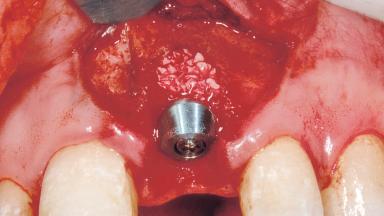

Immediate Placement of an Implant in a Maxillary Left Central Incisor Site

Type of Implants One-Piece

Bone Augmentation Horizontal|Simultaneous

Augmentation Materials Xenogenous|Membrane

Placement Protocol Immediate implant placement

Socket Morphology Single-root socket